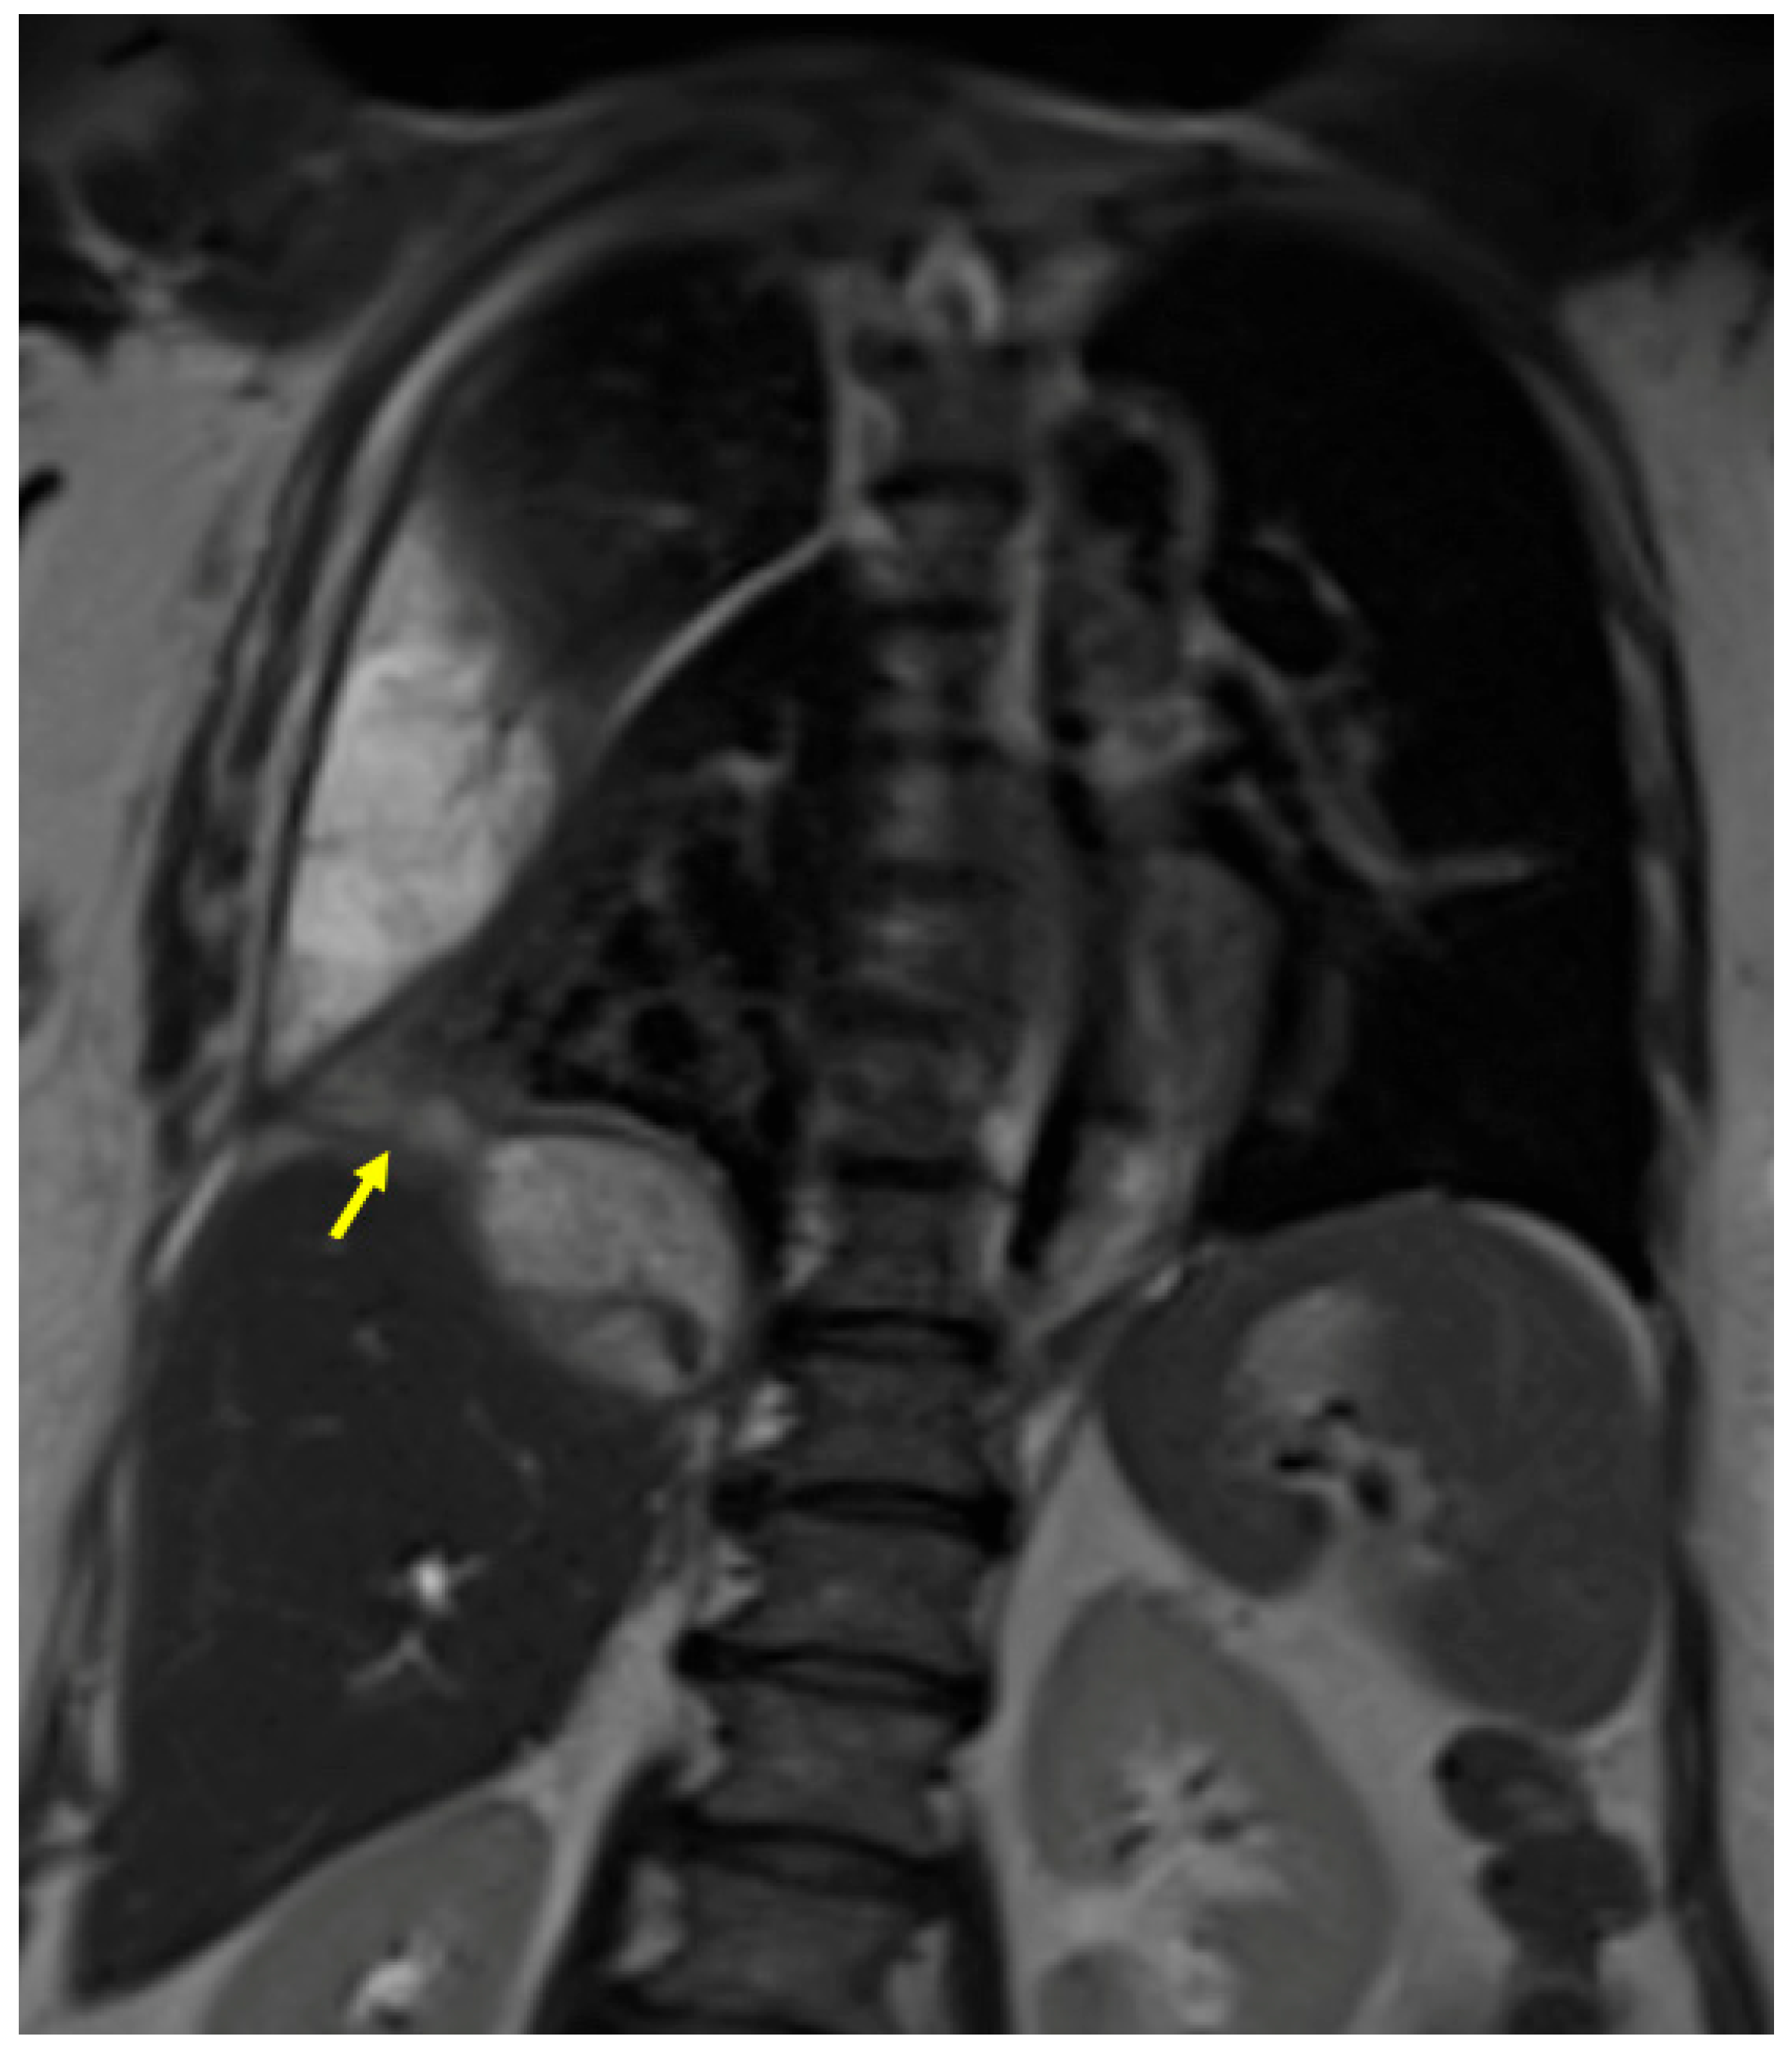

3.1. Case #1: Hepato-Thoracic Fistula

3.2. Case #2: Hepato-Thoracic Fistula

3.3. Case #3: Hepato-Thoracic Fistula

3.4. Case #4: Pancreaticopleural Fistula